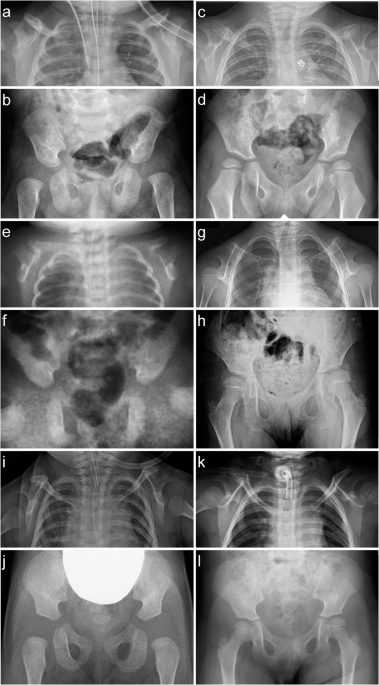

Peripheral afferent neurons – nerves that send signals from all areas of the body to the central nervous system (brain and spinal cord) – are known to infiltrate and grow within malignant bone tumors called osteosarcomas, often…